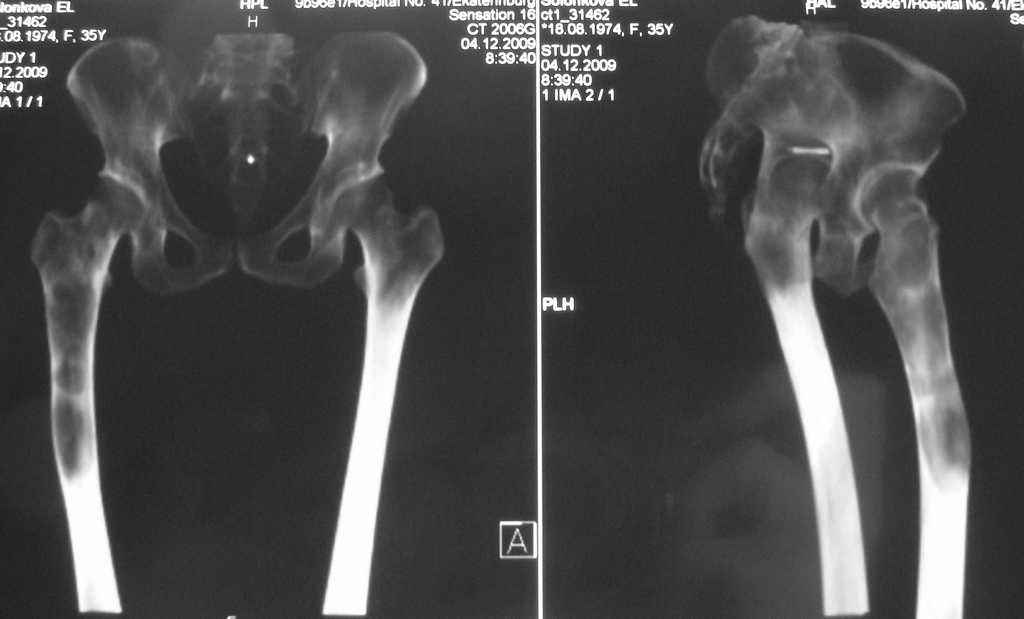

Re: Фиброзная дисплазия-продолжение